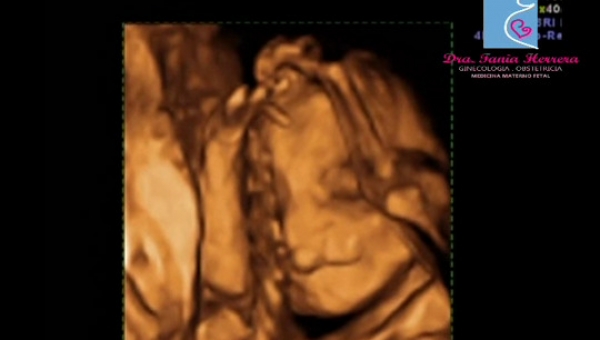

Aunque no se conoce el nivel de incidencia, el embarazo ectópico en cicatriz de cesárea previa puede ocurrir y se presenta como todo un reto para el personal médico especialista que trata el caso.

Es considerada una forma novedosa y potencialmente mortal de implantación anormal de un saco gestacional dentro del miometrio y el tejido fibroso de la cicatriz.